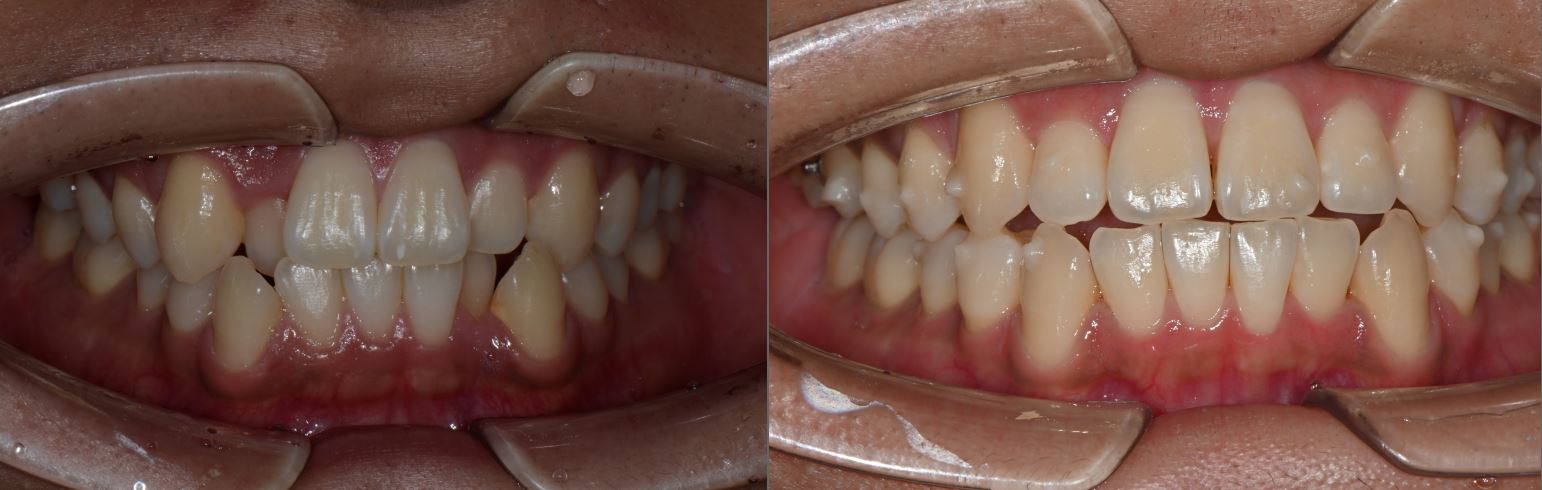

치료전후사진